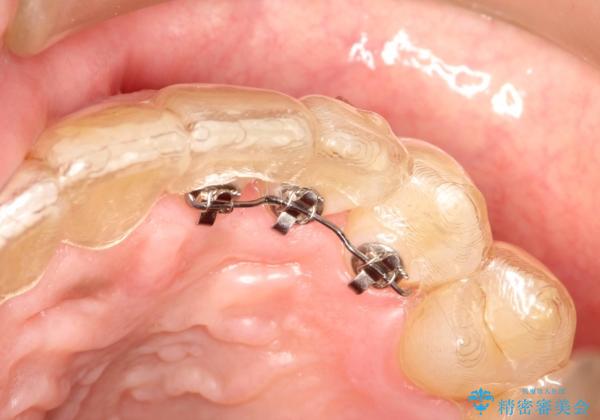

インビザライン invisalign ガタつきを治すマウスピース矯正

- invisalign full

- 非抜歯・上顎臼歯遠心移動によるマウスピース矯正を計画した。